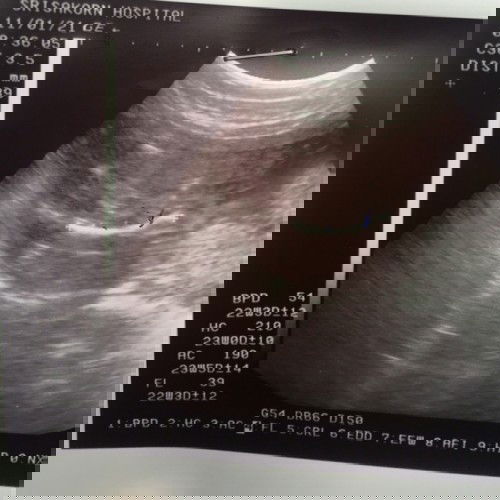

อยากรู้ผลอัตตราซาว

คือหนูท้องได้ 5เดือนกว่าเเล้ว อยากรู้ว่า ผลปกติดีทุกอย่างไหมค่ะ หัวของลูกอยู่ในเกณฑ์ปกติไหมค่ะ กังวลมากค่ะ #ขอบคุณล่วงหน้านะคะ